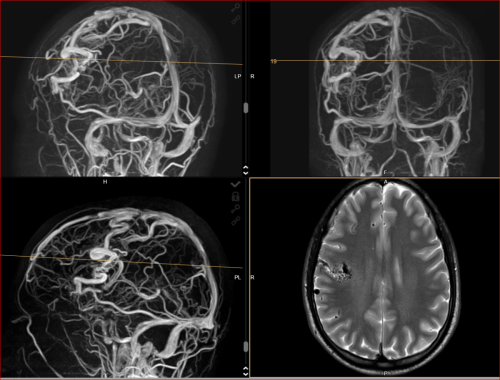

Aneurysma re. 7 mm Darstellung in einer DSA (digitalen Subtraktionsangiographie) links nur ein 2 mm „Baby-Aneurysma“ Im MRT war zuvor das linke Aneurysma aufgefallen, die Auflösung einer DSA ist technisch im MRT nicht erzielbar, beide A. liegen in der ACM Bifurkation jeweils, das re. Aneurysma wurde erfolgreich operiert, das linke Aneurysma wird kontrolliert.